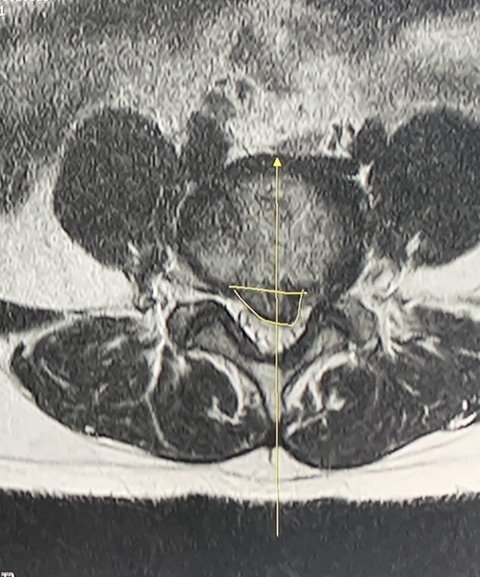

아픈 느낌이 심상치않아 mri 찍을 수 있는 병원으로 갔습니다

그랬더니 디스크가 너무 많이 나와있는 상황이었고 입원 후 검사 진행하고 다음날 시술 받았는데요

그 수업 후로 아파서 연습도 제대로 못했고 시술을 하게 되었어도 제가 기존에 허리디스크 질환이 있었기에 원래 안좋았던곳이 아닌곳이 다른 디스크가 터졌다고 해도( mri로 비교 확인) 그룹수업받으며 많이 좋아져서 필라테스 강사 준비하려했던거라 좋게 마무리하고싶어 필라테스측에 뭐라고 하지도, 할 생각도 없었는데 저렇게 이야기하니까 막 서러워지더라구요